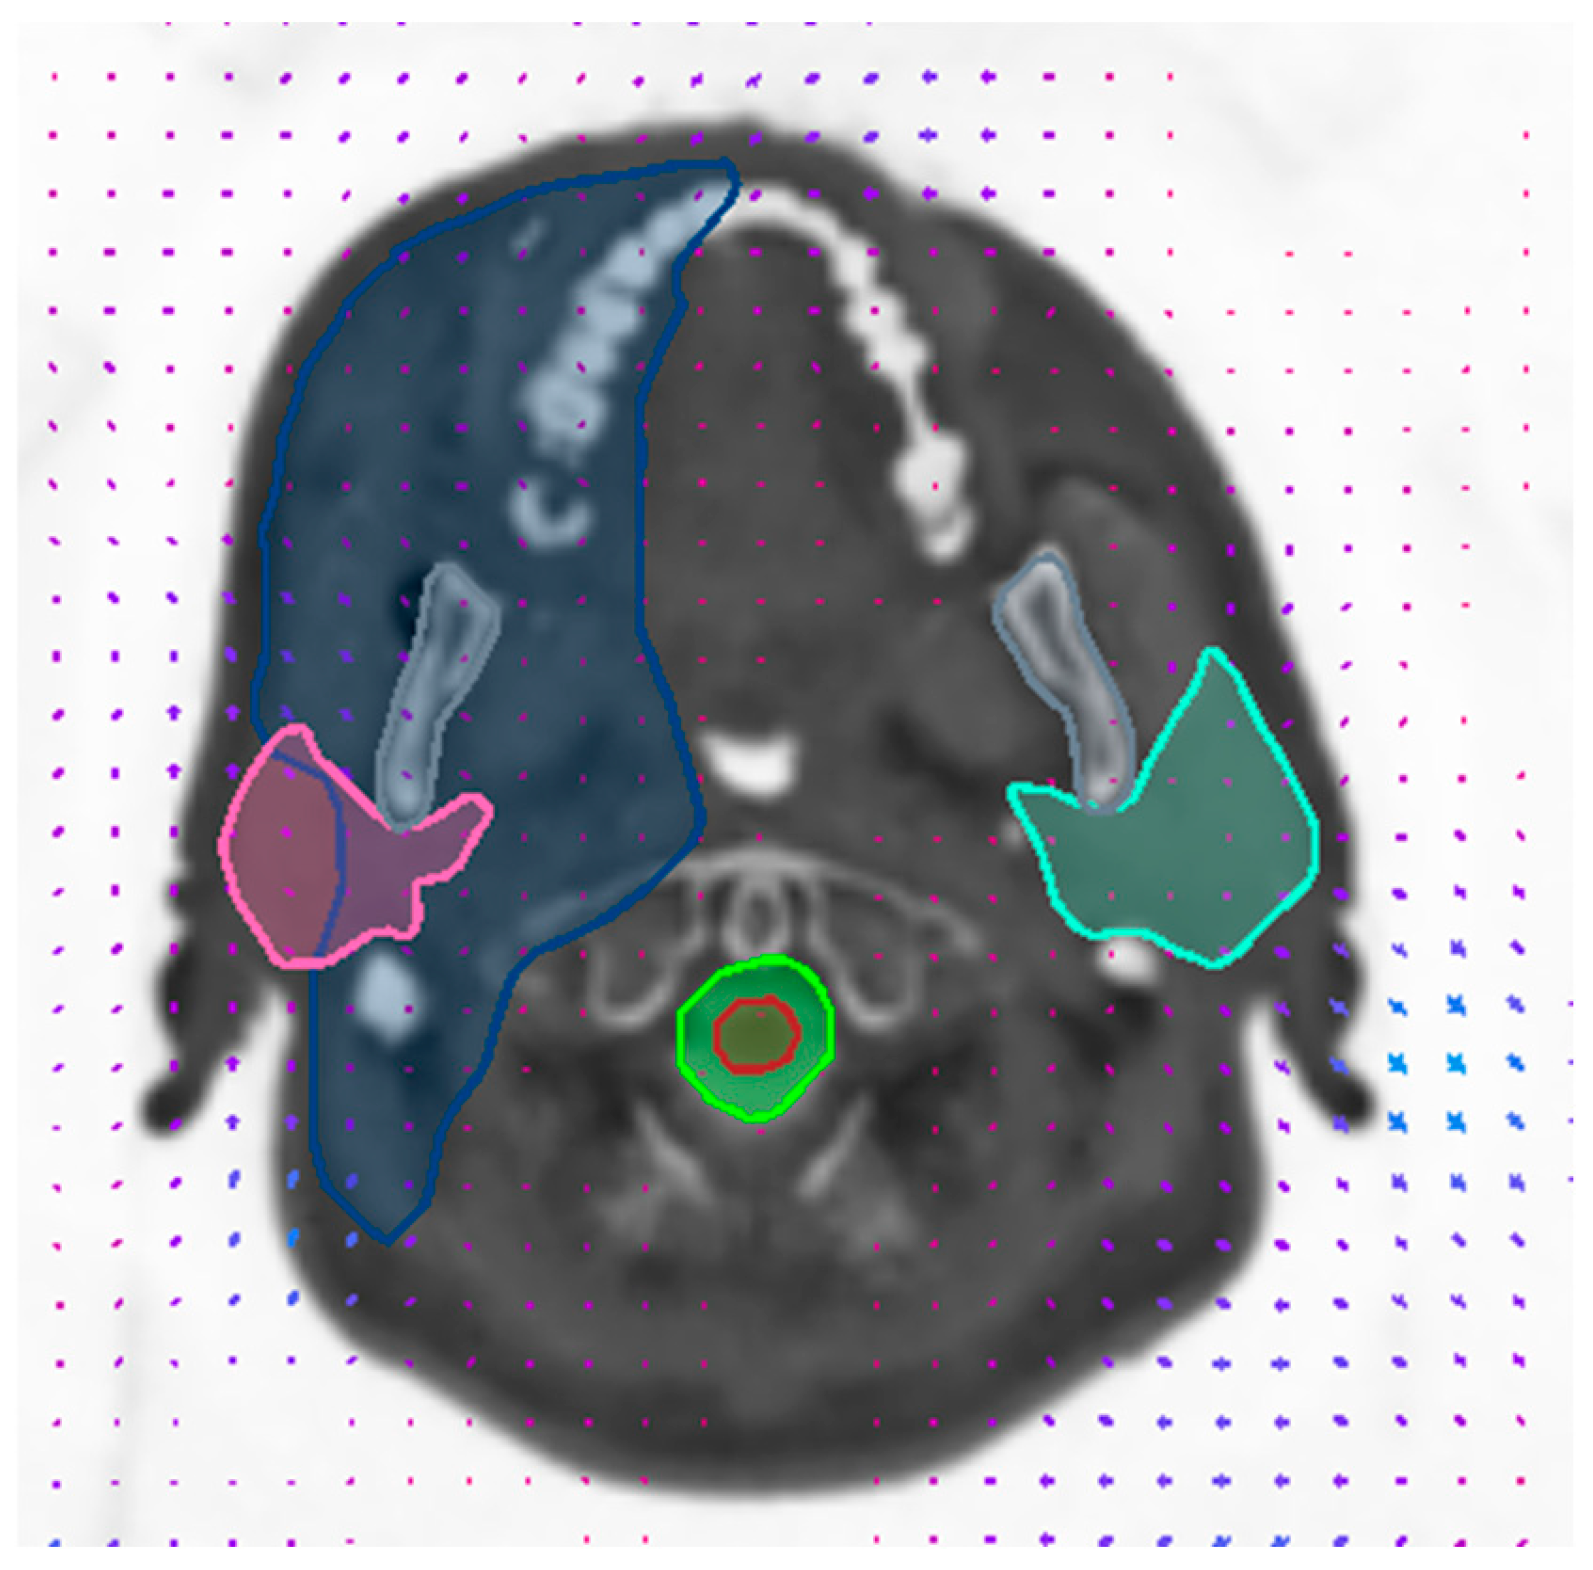

3.2. Validation of Image Registration

| Structure | Mean Warp Magnitude (mm) | Max Warp Magnitude (mm) | Mean Jacobian Determinant | Min Jacobian | Max Jacobian |

|---|---|---|---|---|---|

| Spinal cord | 1.24 | 2.69 | 1.02 | 0.96 | 1.14 |

| Parotid L | 0.76 | 1.59 | 1.07 | 0.99 | 1.16 |

| Parotid R | 1.09 | 1.52 | 0.98 | 0.9 | 1.06 |

| Larynx | 1.66 | 2.51 | 0.97 | 0.9 | 1.04 |

| Brainstem | 0.76 | 1.07 | 0.98 | 0.94 | 1.02 |

| Eye R | 0.51 | 1.07 | 1.03 | 0.97 | 1.07 |

| Eye L | 0.82 | 1.1 | 1.02 | 0.99 | 1.05 |

| Lens R | 0.38 | 0.52 | 1.04 | 1.02 | 1.05 |

| Lens L | 0.86 | 0.96 | 1.03 | 1.03 | 1.04 |

| PTV | 1.05 | 2.56 | 1.01 | 0.88 | 1.18 |